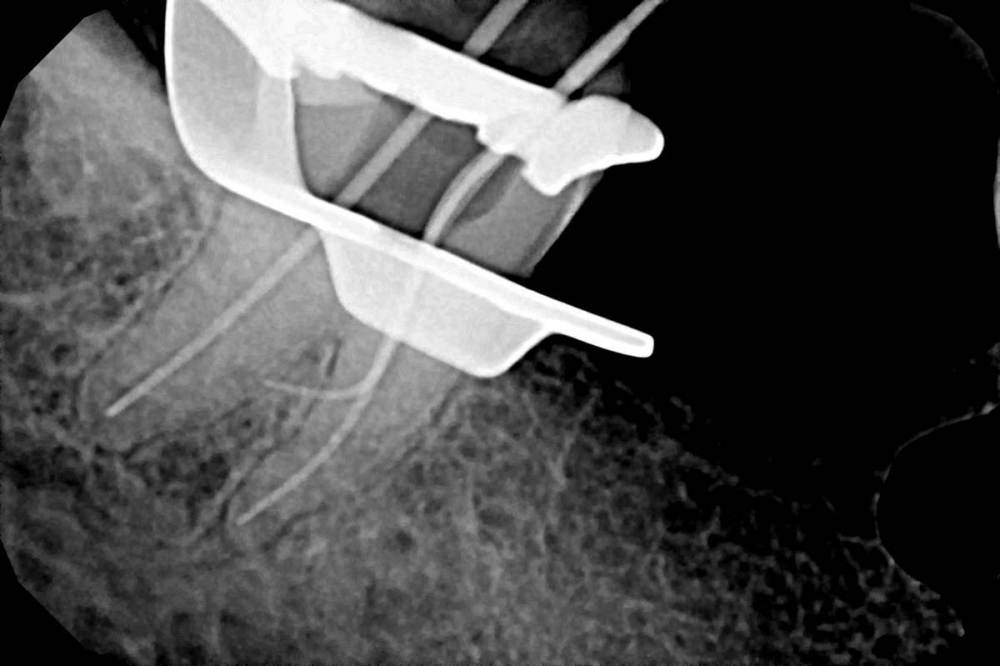

Ico Опубликовано 7 октября, 2022 Автор Поделиться Опубликовано 7 октября, 2022 В первом кейсе все стандартно,просто не каждый день такие антенны попадаются.Во втором 3 изгиба,но их хорошо в ручном режиме берут патфайлы, апексы все соединяются в нижней трети.Третий случай - ретрит со ступенькой был,тут пре рейс 30.06,тоже патфайлы + профайлы 02 конуса,далее шейпинг S1.На четвертом снимке телега не моя,направили помочь.За 1ч15м удалось извлечь фрагмент ,сначала байпас,потом чаком снял кривизну немного,и рядом нарезал площадку,которая позволила озвучить фрагмент сбоку,фрагмент выплыл стандартно. 2 1 2 Ссылка на комментарий